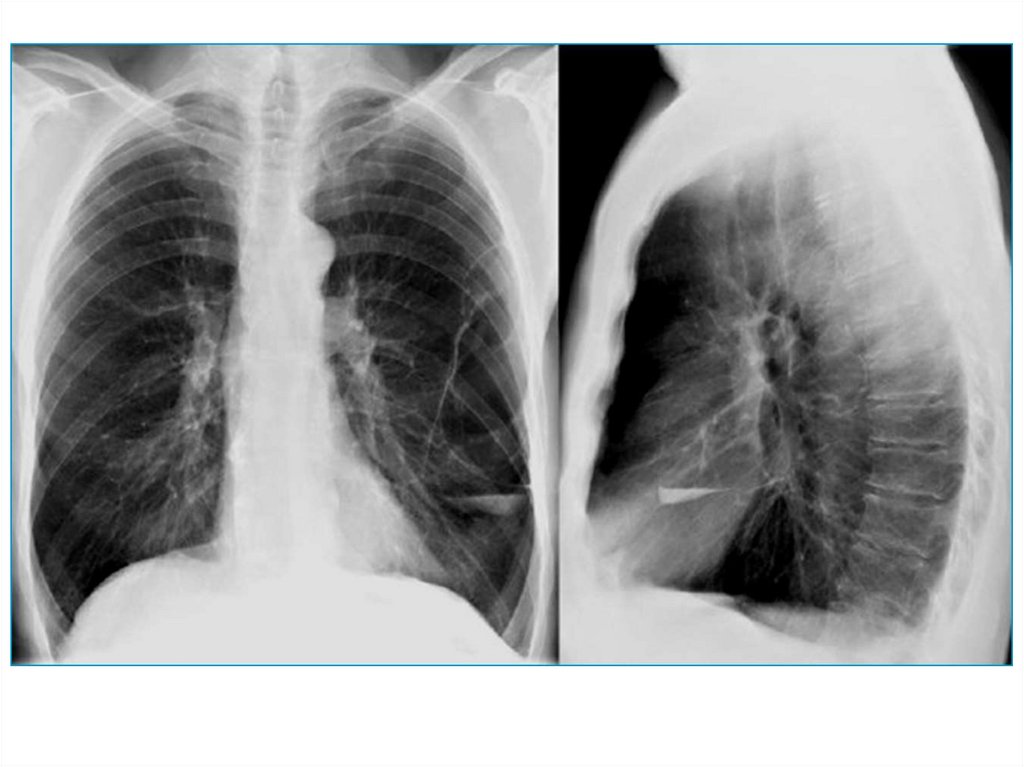

4. Повышенная воздушность

Эмфизема легких – признаки:

• увеличенные легочные поля

• низкое стояние диафрагмы

• грудина смещена кпереди, большое

ретростернальное пространство (на боковом

снимке)